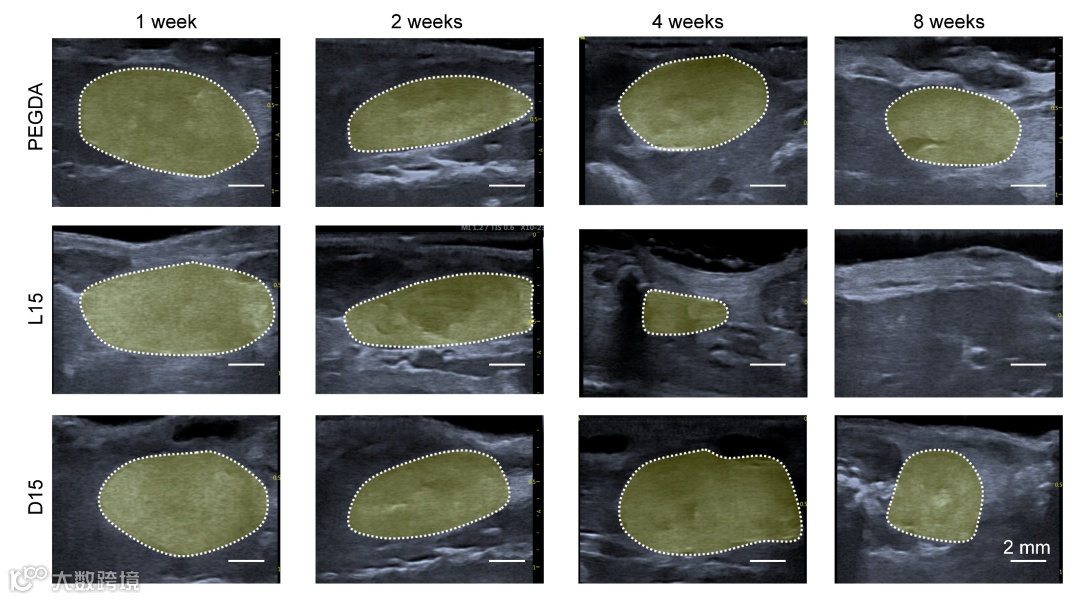

同时,作者也通过高频超声成像证明了通过调节ZIP水凝胶的交联程度或氨基酸单体的光学异构体可以在小鼠皮下模型中实现水凝胶的可控降解(图2)。实验显示PEG水凝胶和D构型的ZIP水凝胶在植入8周内没有发生明显降解,而L构型的ZIP凝胶在8周后完全降解。

图2 ZIP高频超声成像表征植入后水凝胶厚度随时间的变化